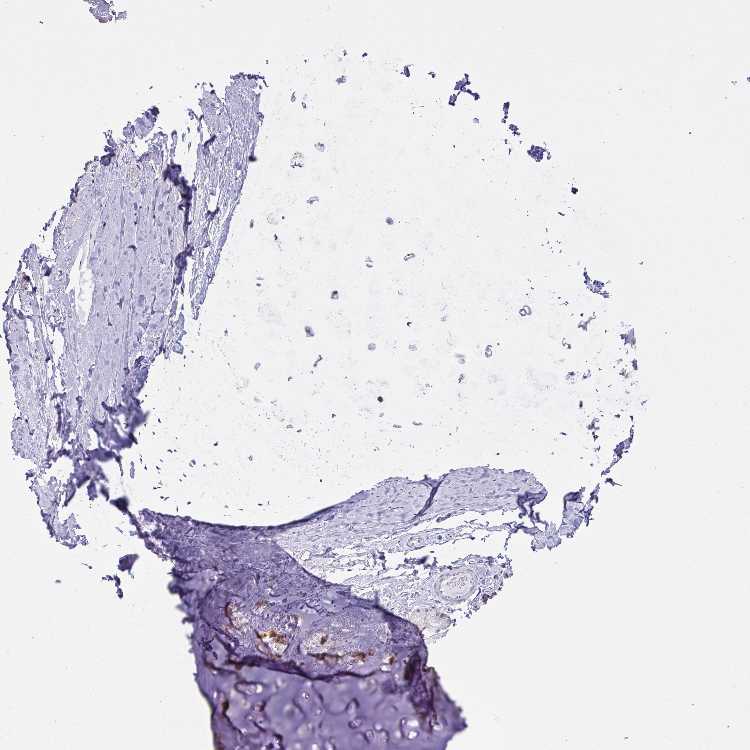

SOFT TISSUE 1 - Antibody stainingi

Antibody staining in the annotated cell types in the current human tissue is reported as not detected, low, medium, or high, based on conventional immunohistochemistry profiling in selected tissues. This score is based on the combination of the staining intensity and fraction of stained cells.

Each image is clickable and will lead to virtual microscopy that enables deeper exploration of all samples and also displays staining intensity scores, fraction scores and subcellular localization as well as patient and tissue information for each sample.

Antibody HPA059101Antibody HPA059790

Chondrocytes HighNot detected

Fibroblasts Not detectedNot detected